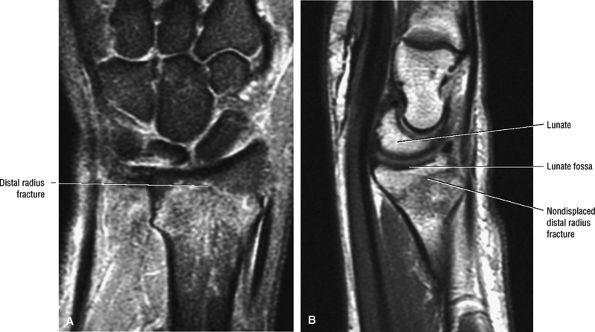

aspect of the lunate fossa. The distal lateral tip of the radius is known as the radial styloid. Fractures through the radial styloid may extend into the scaphoid fossa. Fractures through the lunate and scaphoid fossae can lead to subsequent radiocarpal degenerative arthrosis. Fractures of the ulnar styloid are characterized as occurring either at the distal ulnar styloid or at the base of the ulnar styloid. Fractures that occur at the base of the ulnar styloid can destabilize the ulnar attachments of the TFC, leading to subsequent distal radial ulnar joint instability.